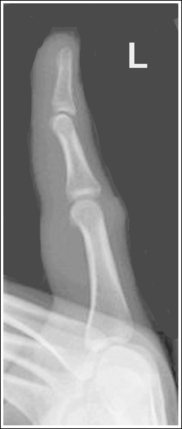

See Figures 4-12 and 4-13 and Box 4-5.

The first digit demonstrates an AP projection. The concavity on both sides of the phalangeal and metacarpal midshafts is equal, as is soft tissue width on both sides of the phalanges.

• An AP projection is accomplished by internally rotating the patient's hand until the thumb is positioned in an AP projection (Figure 4-14). The thumbnail can be used as a reference to determine when the thumb is truly placed in an AP projection. The nail should be positioned directly against the IR and should not be visible on either side of the thumb. A nonrotated AP thumb projection demonstrates equal concavity on both sides of the phalangeal and metacarpal midshafts, as well as equal soft tissue widths on both sides of the phalanges.

• Detecting thumb rotation.When the thumb is rotated away from an AP projection, the amount of midshaft concavity increases on the side of the thumb toward which the anterior surface rotates and decreases on the side toward which the posterior surface rotates. The same observation can be made about the soft tissue surrounding the phalanges when the thumb is rotated. More soft tissue width is evident on the side toward which the anterior surface is rotated, and less soft tissue width is seen on the side toward which the posterior surface is rotated (see Image 10).

Image 10

The long axis of the thumb is aligned with the long axis of the collimated field.

• Aligning the long axis of the thumb with the long axis of the collimator's longitudinal light line enables you to collimate tightly without clipping the distal phalanx or proximal metacarpal (see Image 11).

The IP, MP, and carpometacarpal (CM) joints are visible as open joint spaces, and the phalanges are not foreshortened.

• The IP, MP, and CM joint spaces are open, and the phalanges are demonstrated without foreshortening as long as the thumb is positioned flat against and placed parallel with the IR and the central ray was perpendicular to and centered with the MP joint space. This positioning aligns the joint spaces parallel with the central ray and perpendicular to the IR and positions the long axes of the phalanges perpendicular to the central ray and parallel with the IR. These relationships change when the thumb is flexed or posteriorly extended (hitchhiker's thumb) for the image. Thumb flexion and extension foreshorten the phalanges and superimpose them over the joint spaces (see Image 12).

Image 12

Superimposition of the medial palm soft tissue over the proximal first metacarpal and the CM joint is minimal.

• Minimal soft tissue overlap occurs when the medial palm surface is drawn away from the thumb. It may be necessary to use the patient's other hand as an immobilization device to maintain good positioning of the medial palmar surface. If the medial surface of the palm is not drawn away from the thumb, the soft tissue and possibly the fourth and fifth metacarpals obscure the proximal first metacarpal and CM joint (see Image 13).

Image 13

The MP joint is at the center of the exposure field. The distal and proximal phalanges, the metacarpal, and the CM joint are included within the collimated field.

• Center a perpendicular central ray to the MP joint, which is located where the palm's interconnecting skin attaches to the thumb, to place it in the center of the image. Open the longitudinal collimation to include the distal phalanx and CM joint. Transversely collimate to within 0.5 inch (1.25 cm) of the thumb skin line.

The soft tissue width and the concavity of the phalangeal and metacarpal midshafts are not the same on both sides. The side next to the fingers demonstrates more concavity. The hand was internally rotated too far, demonstrating the thumb in an AP oblique projection.

Decrease the internal hand rotation until the thumb is in an AP projection. The thumbnail should be resting against the IR and should not be visible on either side of the thumb.

The long axis of the thumb is not aligned with the long axis of the collimated field. Note that the proximal metacarpal and the CM joint are clipped.

The distal phalanx is foreshortened, and the IP joint space is closed. The MP joint was elevated off the IR and the distal thumb was posteriorly extended (hitchhiker's thumb).

The fifth metacarpal and the medial palm soft tissue are superimposed over the proximal first metacarpal and CM joint. The medial metacarpal and palmar surface have not been drawn away from the thumb.

Using the patient's other hand or another immobilization device, draw the medial side of the hand and palmar surface away from the thumb. Make sure that the thumb does not rotate away from an AP projection with this movement and that the patient's opposite hand is not included in the exposure field.